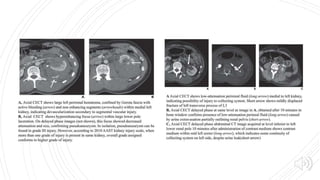

Include injuries to

renal parenchyma

and collecting

system as well as

vascular injuries.

Lacerations

extending deep to

involve the

collecting system

with urinary

extravasation are

included.

Delayed imaging

usually shows

urine leaking into

the perirenal

space

Grade I GradeII Grade III Grade IV Grade V Contusions and subcapsular hematoma are key terms used In the identification Perinephric hematomas & renal parenchymal lacerations are key terms Are deeper lacerations (>1cm) that do not result in urine leak. Any injury occurring in the presence of a vascular injury Include injuries to renal parenchyma and collecting system as well as vascular injuries. Shattered kidney, avulsion or laceration of the main renal artery , vein and devascularised kidney with active bleeding Contusions appear on portal venous phase CT images as globular, ovoid or round poorly demarcated area of relatively poor enhancement Hematomas contained within the gerota fascia has been postulated to have a tamponade effect on renal bleeding, resulting in perinephric clot formation Vascular injuries include pseudoaneurysm or arteriovenous fistula. Lacerations extending deep to involve the collecting system with urinary extravasation are included. Loss of identifiable renal parenchymal anatomy Hilar vascular injuries are not common. Subcapsular hematoma are confined by renal capsule. These are non enhancing cresentric or lentiform shaped fluid collections Lacerations are superficial (<1cm) and there is no urine leak These have been described as a focal collection of vascular contrast enhacement that shows decreasing attenuation with delayed imaging Delayed imaging usually shows urine leaking into the perirenal space Complete arterial tears result in retroperitoneal hematomas with possible active bleeding.